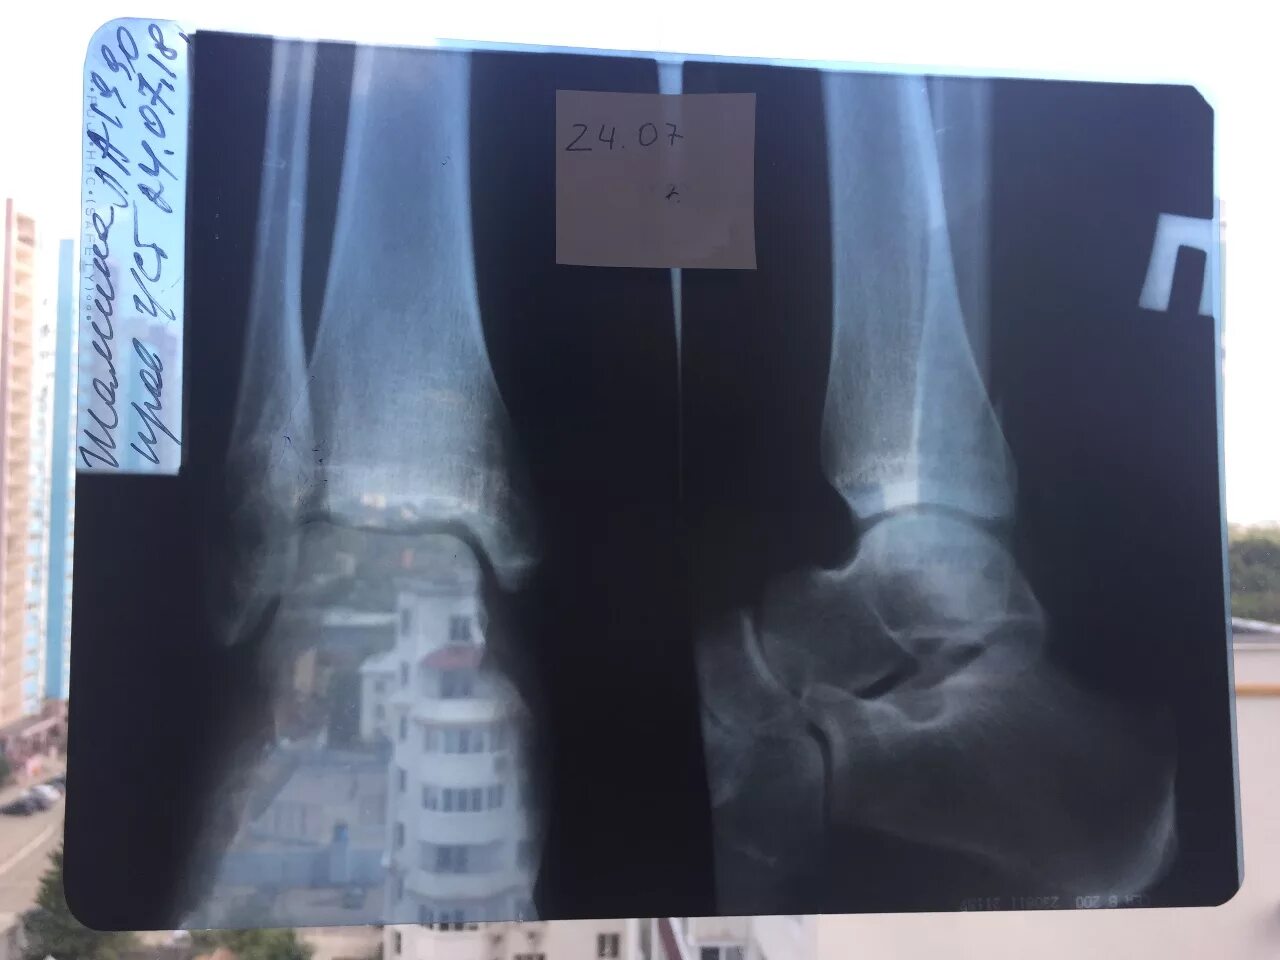

Через сколько срастается перелом лодыжки